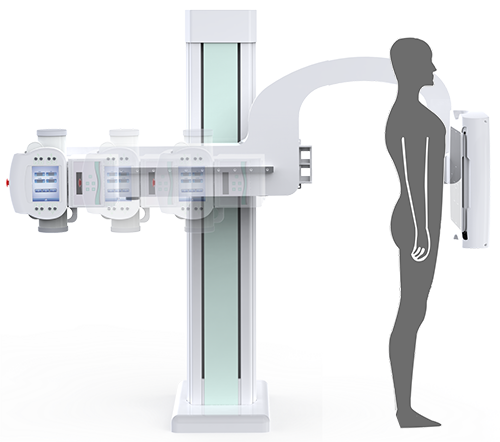

PLD7900

動(dòng)態(tài)U臂DR

多功能動(dòng)態(tài)平板DR,采用U型臂結(jié)構(gòu),具有靜態(tài)DR攝影、數(shù)字透視、數(shù)字造影和可視化攝影的功能。

電動(dòng)旋轉(zhuǎn)內(nèi)平衡結(jié)構(gòu),可實(shí)現(xiàn)快捷擺位,滿足特殊體位的靜態(tài)與動(dòng)態(tài)檢查。

滿足不同身高的受檢者快速地進(jìn)行胸片的靜態(tài)及動(dòng)態(tài)檢查,適合大規(guī)模體檢。

SID可拉伸至1.8米,滿足標(biāo)準(zhǔn)胸片、職業(yè)性塵肺病檢查等特殊需求。